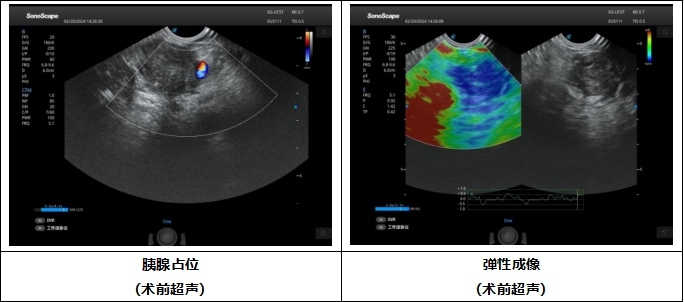

中年男性患者,腹痛3月,多次影像学检查提示胰腺病变,但具体良恶性质一直未能得到明确。由于胰腺位置深,经皮穿刺很多情况下无法获取胰腺肿瘤标本,而超声内镜技术可在胃或十二指肠内以最近的距离对胰腺进行扫查,并进行穿刺活检。经白云医院消化内科会诊后,及时安排实施超声内镜引导下细针穿刺术(EUS-FNA),医院消化内科刘朋副主任用精湛医术护佑生命健康,手术顺利完成,术中在超声内镜扫查下已基本诊断为恶性肿瘤,术后穿刺组织条在病理科医师耐心、专业的阅片后确诊为胰腺癌,病变的良恶性终于明确,患者也即将进行肿瘤专科治疗。

“4E”技术是指消化内镜难度较大的4类手术,包括:EUS(超声内镜)、ESD(内镜粘膜下剥离术)、EVL(内镜下食管静脉曲张套扎术)、ERCP(经内镜逆行胰胆管造影术) 。超声内镜(EUS)是将内镜和超声相结合的消化道检查技术,将微型高频超声探头安置在内镜顶端,当内镜插入体腔后,在内镜直接观察消化道黏膜病变的同时,可利用内镜下的超声行实时扫描,可以获得胃肠道的层次结构的组织学特征及周围邻近脏器的超声图像。超声内镜引导下细针穿刺(EUS-FNA)就是在超声内镜引导下运用一根纤细的活检针经过内镜活检孔道对相应病变进行抽吸活检,通过活检,可以获得病灶的细胞、组织学诊断,从而明确病变性质。